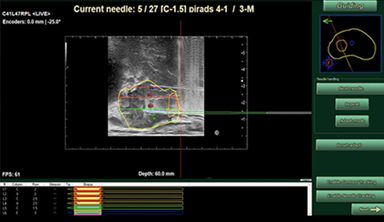

Needle Pre-planning

Systematic Needles Pre-planning

(with Anatomical Biopsy Model)

Needle Pre-planning Rendering

Navigation of Target Biopsy